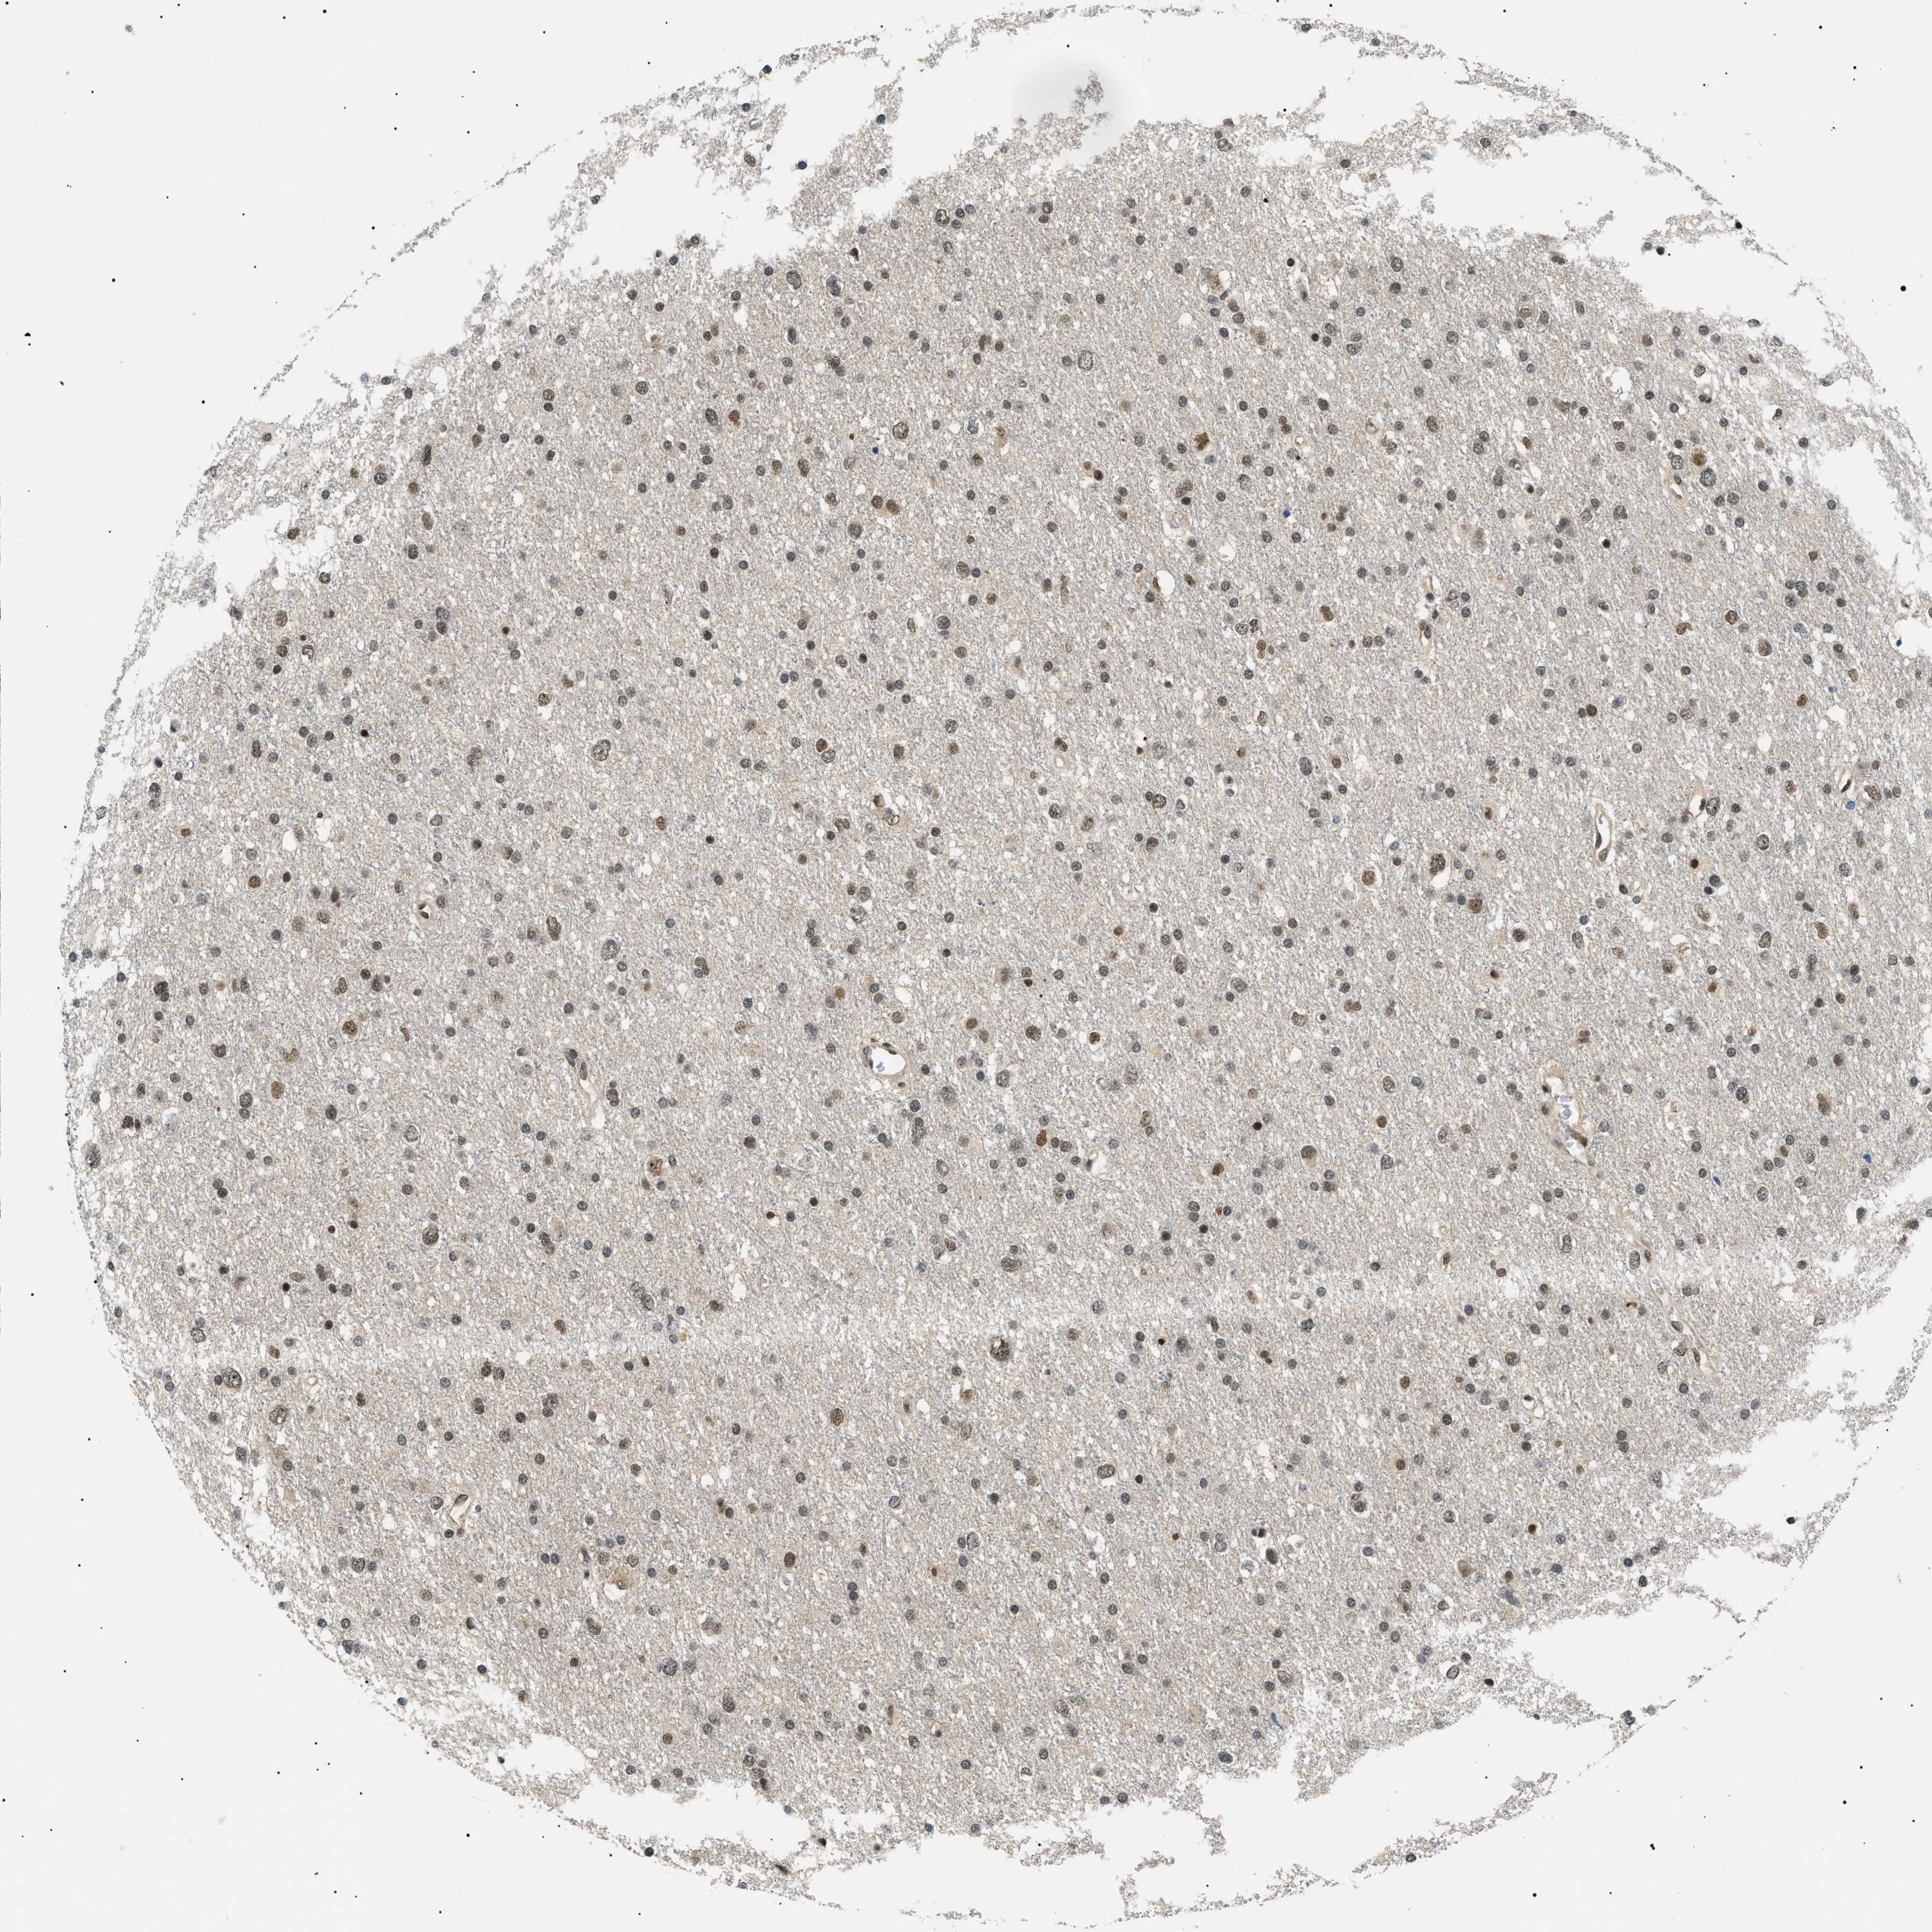

GLIOMA - Protein expressioni

A mouse-over function shows sample information and annotation data. Click on an image to view it in a full screen mode. Samples can be filtered based on level of antibody staining by selecting one or several of the following categories: high, medium, low and not detected. The assay and annotation is described here.

Note that samples used for immunohistochemistry by the Human Protein Atlas do not correspond to samples in the TCGA dataset.

Antibody stainingi

Antibody staining in the annotated cell types in the current human tissue is reported as not detected, low, medium, or high, based on conventional immunohistochemistry profiling in selected tissues. This score is based on the combination of the staining intensity and fraction of stained cells.

Each image is clickable and will lead to virtual microscopy that enables deeper exploration of all samples and also displays staining intensity scores, fraction scores and subcellular localization as well as patient and tissue information for each sample.

Antibody HPA019824

Antibody CAB015201

Staining

High

Medium

Low

Not detected

Intensity

Strong

Moderate

Weak

Negative

Quantity

>75%

75%-25%

<25%

None

Location

Nuclear

Cytoplasmic/membranous

Cytoplasmic/membranous,nuclear

Glioma, malignant, High grade

Glioma, malignant, Low grade